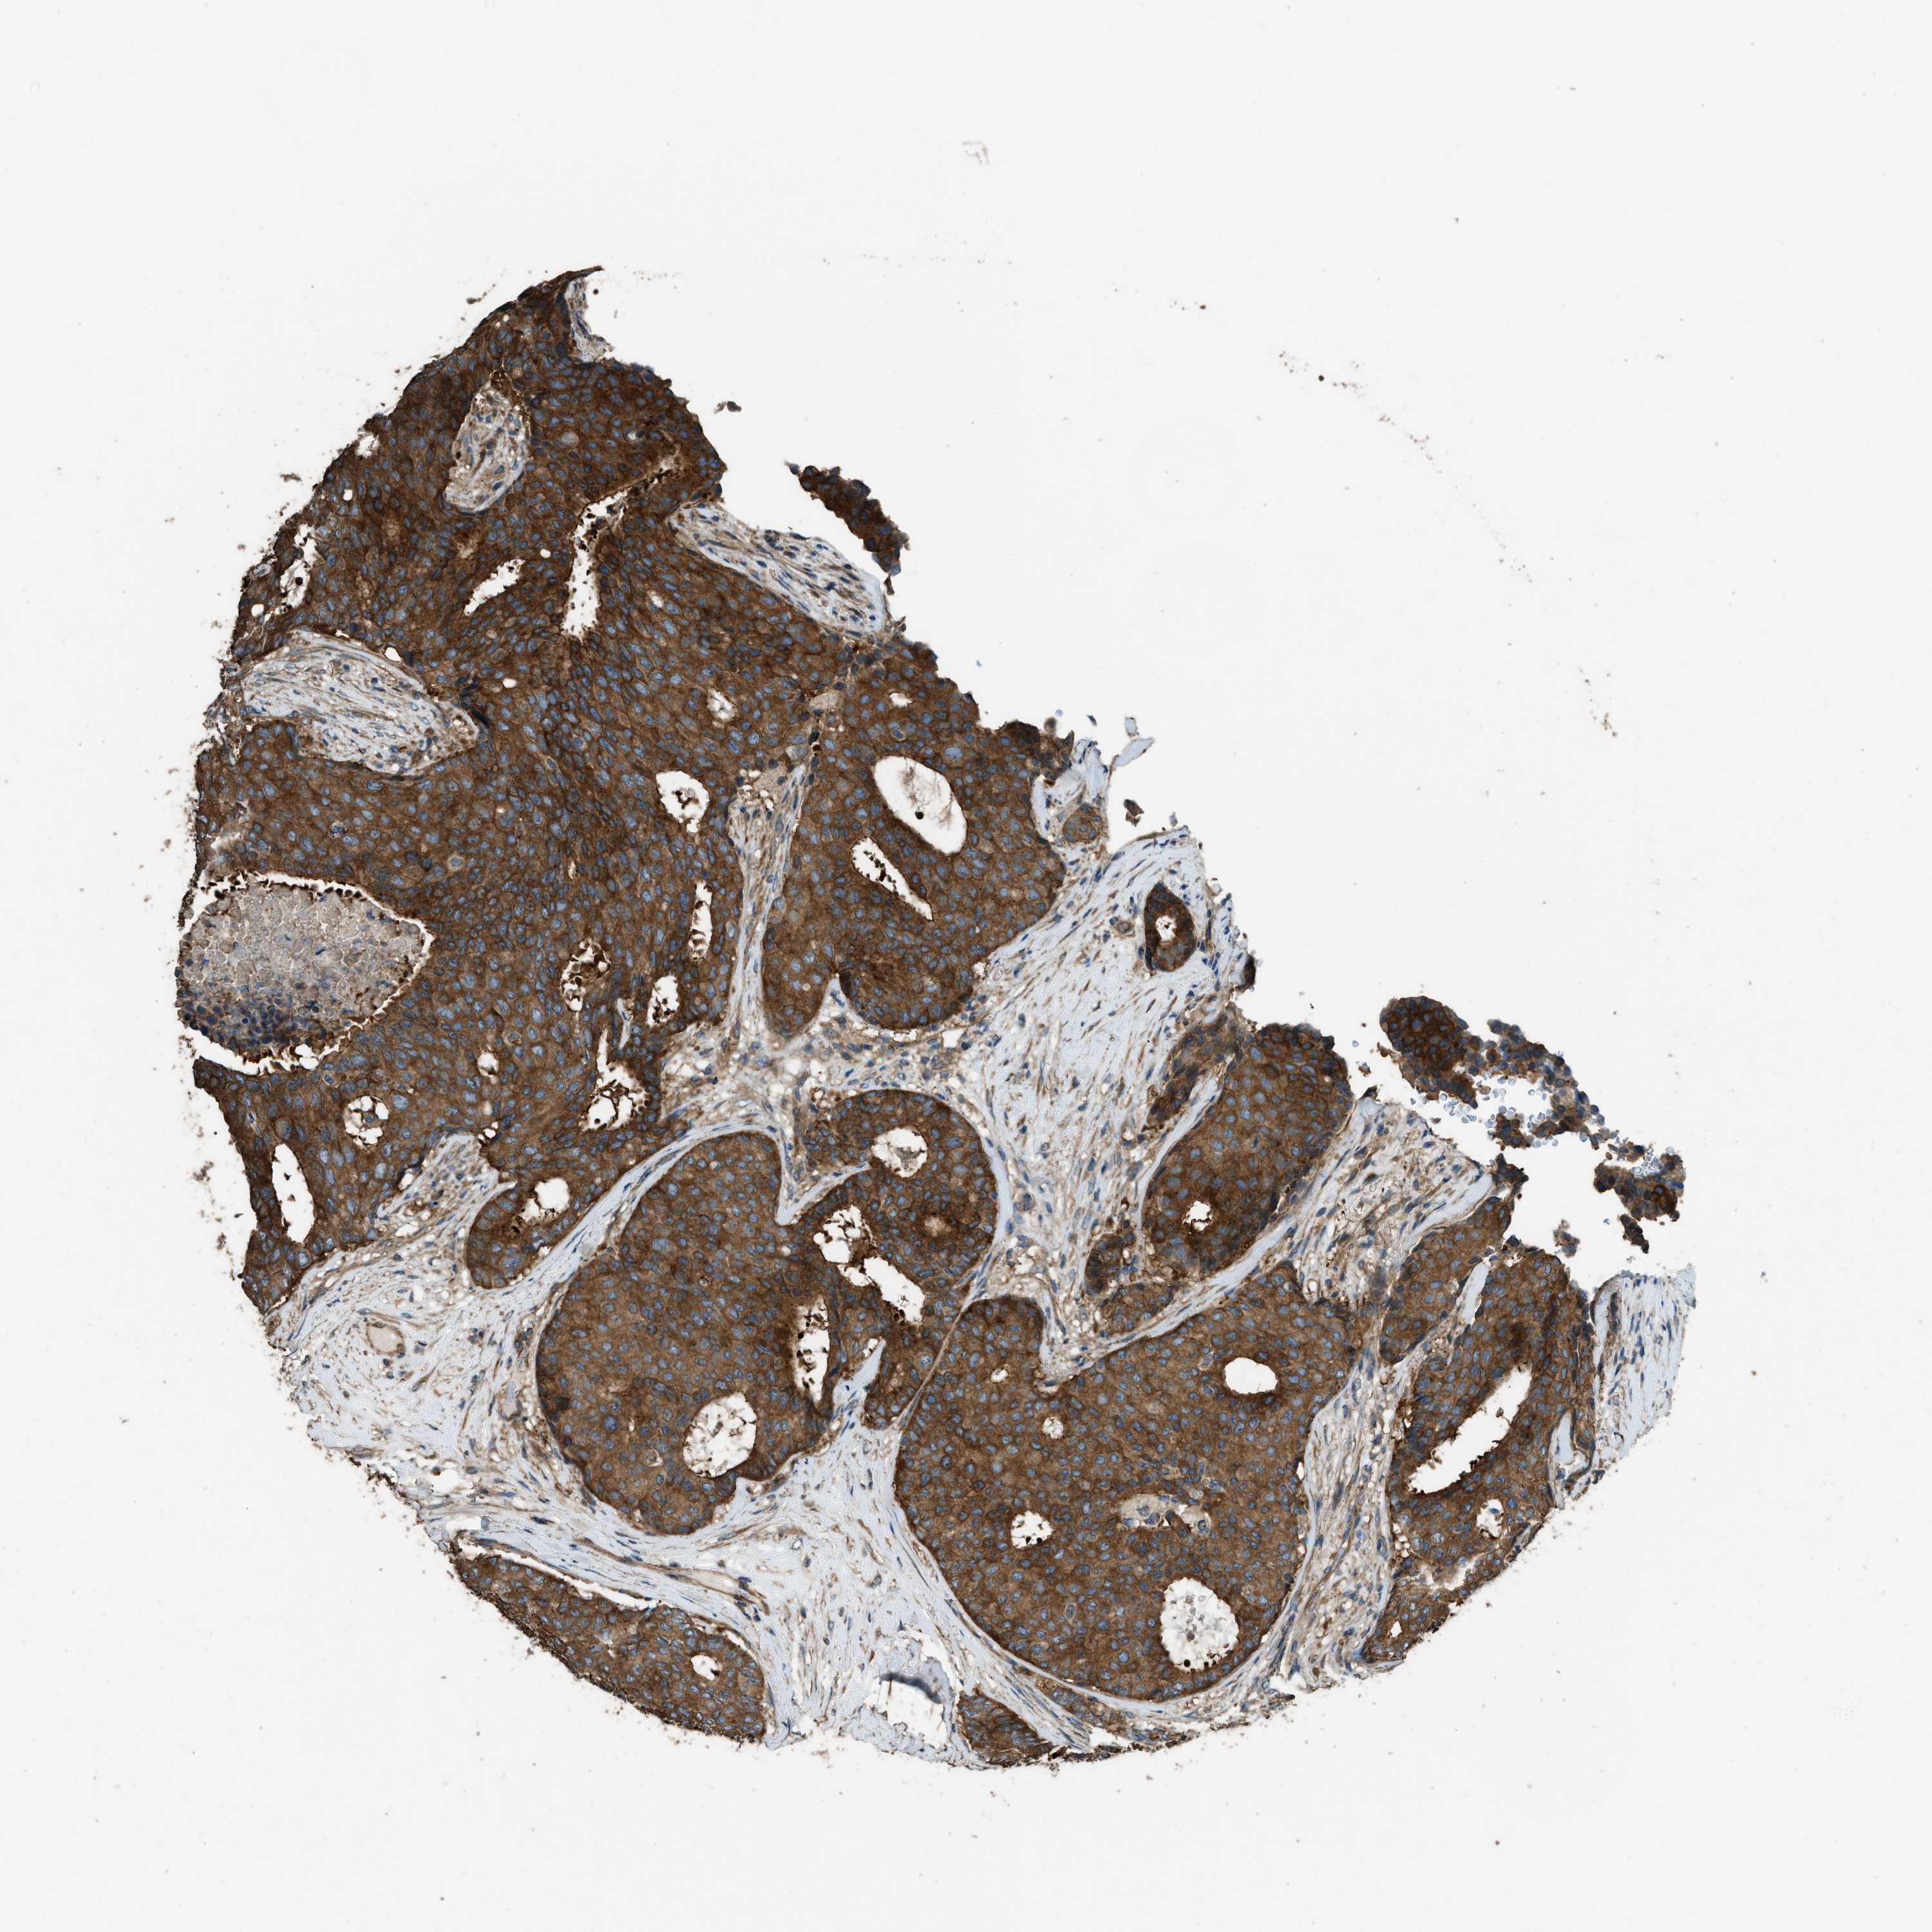

CANCER BREAST CANCER Show tissue menu

BRCA TCGA BRCA VALIDATION PROTEIN EXPRESSION